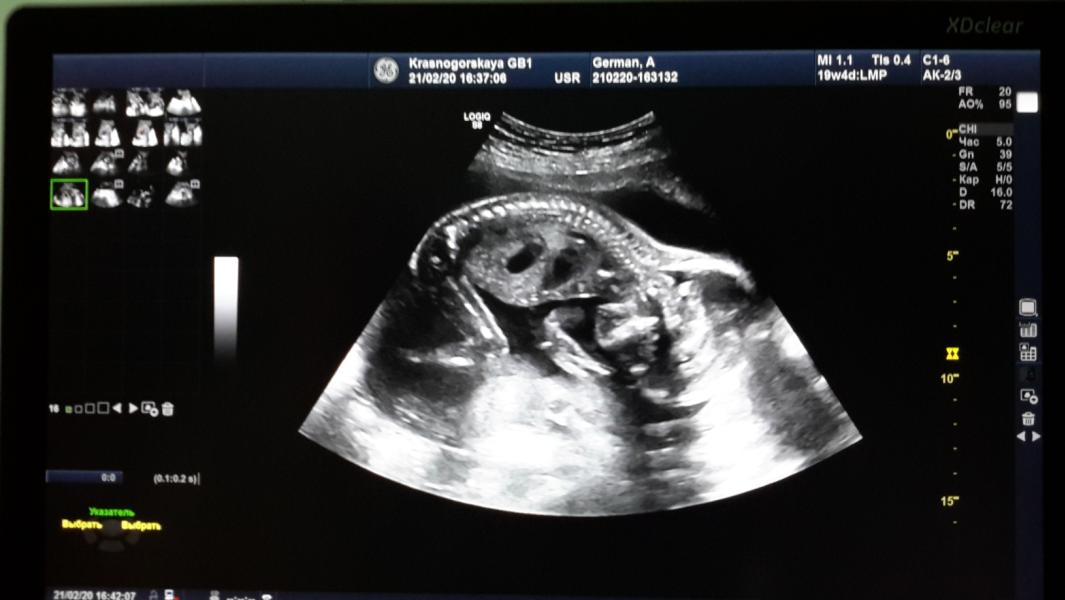

20 недель!!! 20, Карл!!! Как же летит время 🙈🙈🙈.. Малыш 360 г. Маленький пухлый сладыш N2 ❤️